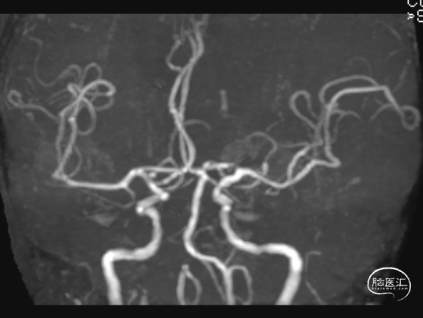

术后第3天患者恶心、呕吐症状消失,仍有头晕,复查DWI及MRA。